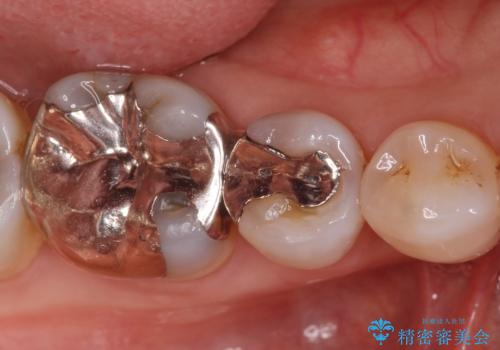

- 口を開けると銀歯が見えるのが嫌とのことで来院。

銀歯を外し、拡大鏡下で虫歯を全て取り除き、白い詰め物(e-maxインレー)にて治療することになりました。

まずは一つ治療したいとの事だったので手前の小臼歯から行いました。